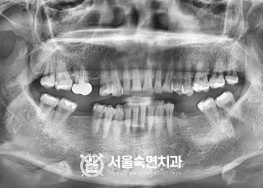

임플란트-치료-전후사진

서울대학교-출신-보건복지부-인증-통합치의학과-전문의-2인-책임관리